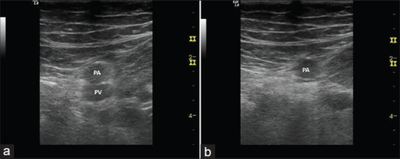

- Popliteal vein

- Start with light pressure to better visualize vessels

- Apply generous compression over the popliteal vessels to test compressibility

- Vein usually superficial to the artery (artery is anterior)

Normal

- An appropriate amount of pressure gives complete collapse of the vein as well as some (but not full) compression of the adjacent artery.[3]